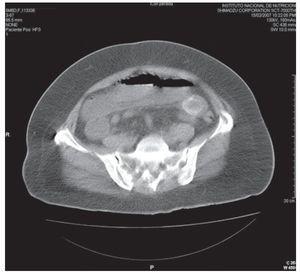

Ingresó al Instituto Nacional de Ciencias Médicas y Nutrición por dolor abdominal de características ya descritas. A la exploración física con dolor abdominal difuso a la palpación profunda y peristalsis disminuida. Los exámenes de laboratorio con 12,000/mm3, neutrófilos de 85%, pruebas de función hepática normales. Se le realizó una placa simple de abdomen con dilatación de asas de intestino delgado y aire en la vesícula biliar (Figura 1). Se le realizó una tomografía computada (TC), la cual mostró dilatación de asas de intestino delgado proximal, imagen hiperdensa intraluminal y zona de transición a este nivel (Figura 2). Se realizó laparotomía exploradora en la cual se evidenció un lito gigante de aproximadamente 6 cm de diámetro en el yeyuno proximal, se le realizó enterotomía con extracción del lito y cierre primario en dos capas (Figura 3).

Figura 1. Placa simple de abdomen con dilatación de asas de intestino delgado y aire en la vesícula biliar